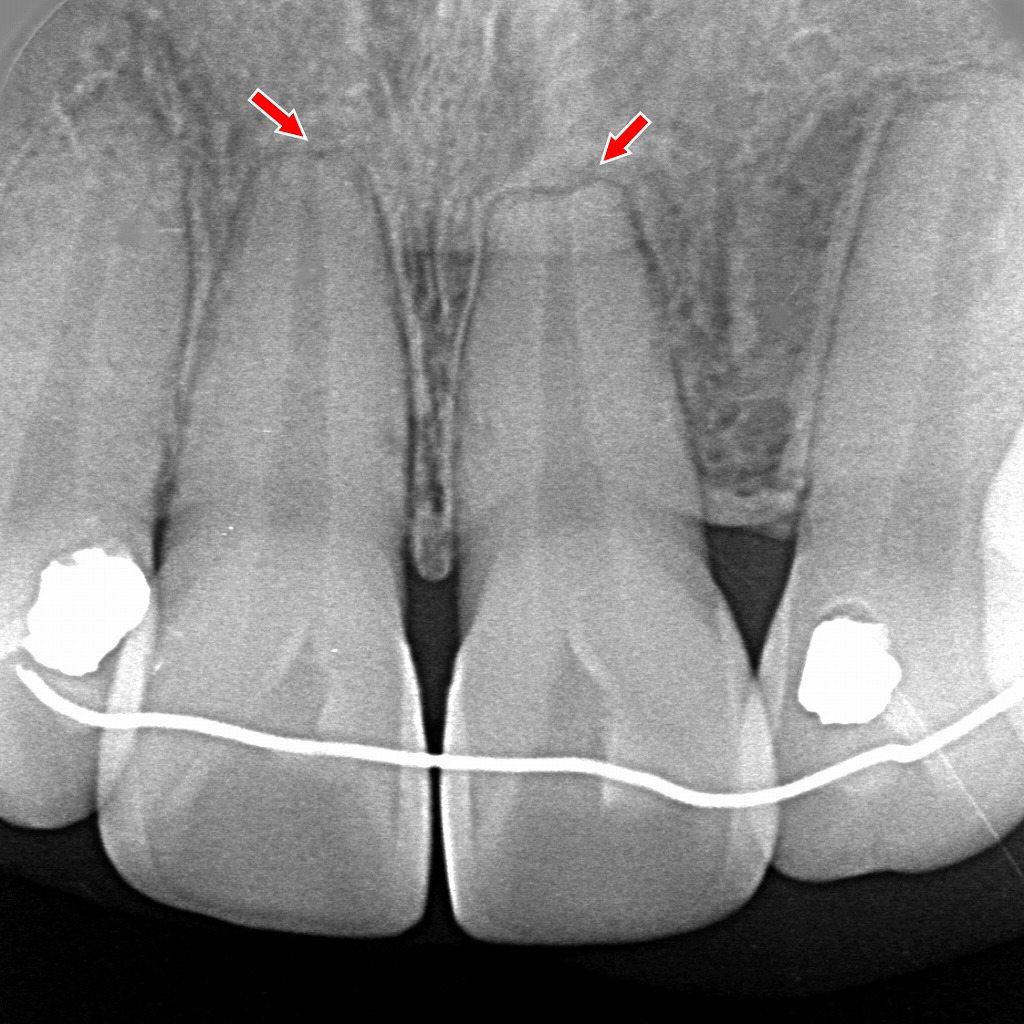

🔍 画像の解説:病的歯根吸収(前歯部)

矢印で示された領域では、前歯の歯根表面が不規則に吸収され、境界の不鮮明な透過像(黒く写る部分)が確認できます。

これは**外部吸収(external resorption)**の典型的な像で、歯根が外側から溶け始めている状態を示唆します。

正常な生理的吸収ではあり得ない位置・形態のため病的歯根吸収と判断される所見です。

🦷 原因は外傷の可能性がある?

前歯部の病的歯根吸収で最も多い誘因のひとつが**過去の外傷(転倒・衝突などによる打撲)**です。

外傷によって歯根膜やセメント質がダメージを受けると、

・破歯細胞(odontoclast)

・破骨細胞(osteoclast)

が活性化し、時間をかけて歯根が徐々に吸収されることがあります。

✔ 外傷が疑われる理由

- 前歯は外傷の頻度が高い

- 外傷後は長期(数年後)に遅発性吸収を起こすことがある

- 画像では外側に向かう不規則な吸収像がみられ、外傷性吸収の典型パターン

画像単独では「外傷が最も疑われる所見」ですが、

臨床歴(転倒・ぶつけた記憶、変色、打診痛の既往など)があれば確度はさらに高まります。